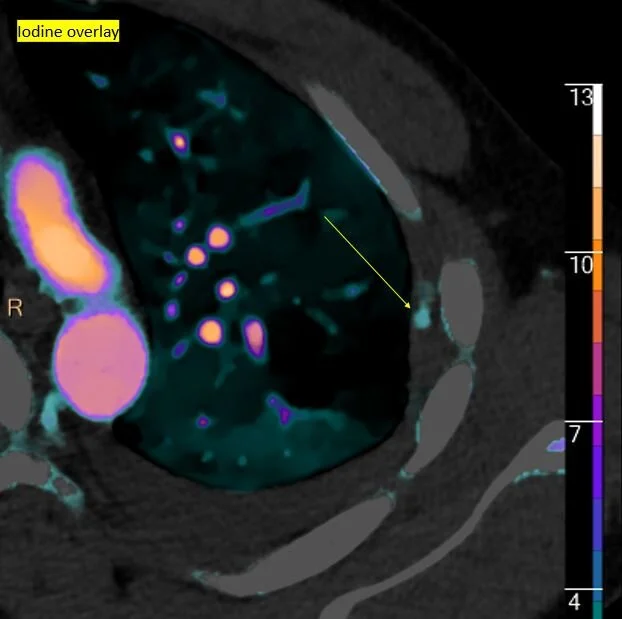

Iodine map shows small focus of active bleed (yellow arrow)

Iodine overlay confirms the finding. This is what bled a few days later.